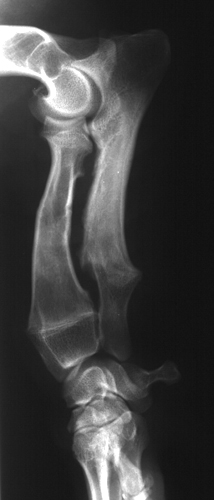

Obr.2: Mírně vyvinutý syndrom radius curvus, viditelné zakřivení

radia a deformace loketního kloubu.